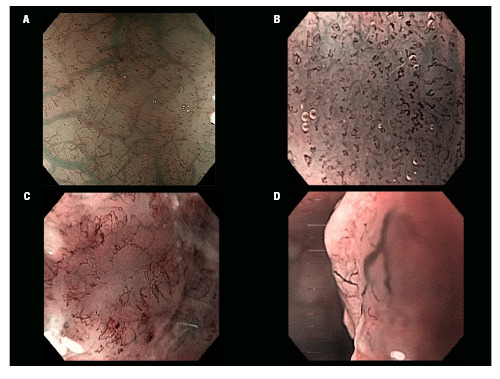

Background: Accurate evaluation of the invasion depth of superficial esophageal squamous cell carcinoma (SESCC) is crucial for optimal treatment. While magnifying endoscopy (ME) using the Japanese Esophageal Society (JES) classification is reported as the most accurate method to predict invasion depth, its efficacy has not been tested in the Western world. This study aims to evaluate the interobserver agreement of the JES classification for SESCC and its accuracy in estimating invasion depth in a Brazilian tertiary hospital.

Methods: We retrospectively selected ME with Narrow Band Imaging (ME-NBI) images of 30 suspected SESCC cases. The best images of each case were included in online forms, which were evaluated by ten endoscopists (five experts and five novices). The evaluators classified the lesions according to the JES-IPCL classification and estimated the depth of invasion. Interobserver agreement was assessed using kappa values. Histological comparison was possible for 17 lesions.

Results: The overall interobserver agreement for the JES-IPCL classification was moderate (K=0.455, P<0.001). Agreement among experts (K=0.437) and novices (K=0.483) was also moderate. Sensitivity, specificity, and accuracy for IPCL types were: B1 (41.3%, 78.9%, 59.9%), B2 (75%, 66.7%, 68.7%), and B3 (46%, 91.7%, 78.6%). Overall accuracy of the JES classification for estimating depth of invasion was 47.5%.

Conclusion: The moderate interobserver agreement suggests the JES-IPCL classification may be useful in the Western world, but extensive training is needed. The findings indicate a longer learning curve for accurate ME-NBI image evaluation using the JES classification.